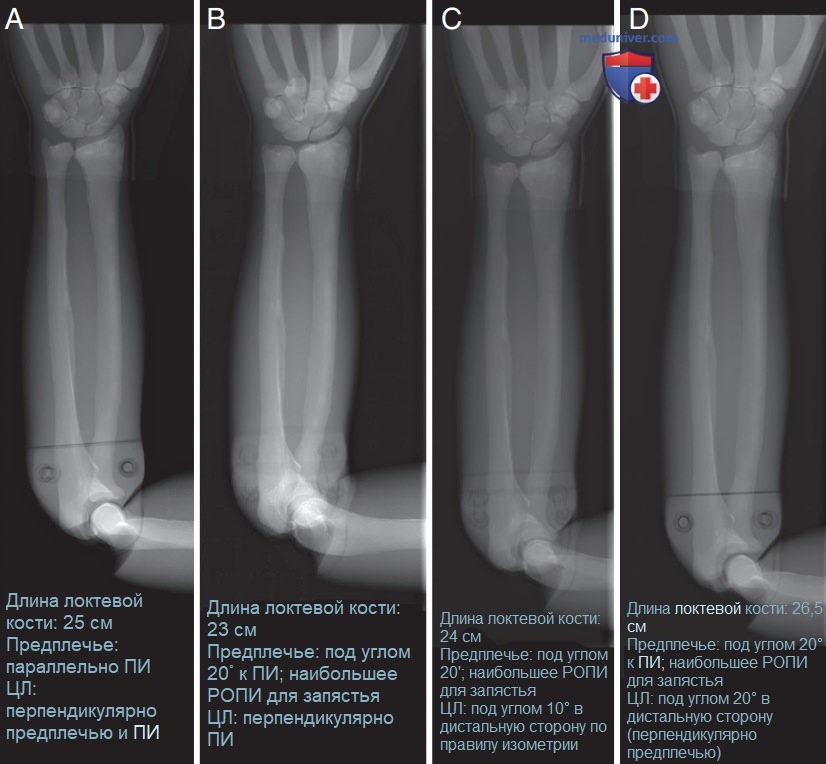

Рисунок 5. Варианты укладки предплечья для получения рентгенограммы оптимального качества. (А) Оптимальное расположение ЦЛ, предплечья и ПИ. (B) Проекционное укорочение предплечья вследствие его наклона. (C) Укладка предплечья по правилу изометрии. (D) Элонгация предплечья, когда ЦЛ наклонен так, чтобы образовать прямой угол с предплечьем и ПИ.

г) Исследование длинных костей. Чтобы получить изображение длинных костей с наименьшей дисторсией и оптимальным взаимным расположением анатомических структур, необходимо направить ЦЛ перпендикулярно, а ПИ параллельно длинной оси кости (рис. 5, А; также см. рис. 8). Если пациента невозможно уложить так, чтобы длинная кость располагалась параллельно ПИ, взаимное расположение ЦЛ, ПИ и кости определит выраженность и тип дисторсии полученного изображения, а также повлияет на взаимное расположение анатомических структур на изображении. На рис. 5, Б представлена рентгенограмма дистального отдела предплечья в ЗП проекции, при получении которой длинная ось предплечья была наклонена под углом 20° к ПИ, а ЦЛ был ориентирован перпендикулярно ПИ. Такая укладка является наименее удачной, поскольку приводит к наибольшему проекционному укорочению и худшему взаимному расположению суставных поверхностей. Сравните длину предплечья и расположение костей, образующих локтевой сустав, на рис. 5, А и Б. Изображение предплечья на рис. 5, В было получено по правилу изометрии (рис. 6). В соответствии с этим правилом, чтобы минимизировать проекционное укорочение, ЦЛ должен быть установлен на угол, равный половине угла между объектом и ПИ.

Например, если пациент при рентгенографии бедренной кости в ПЗ проекции не может полностью разогнуть колено, и бедренная кость располагается под углом 30° к ПИ, а дистальный ее отдел лежит на большем расстоянии от источника излучения, чем проксимальный, то ЦЛ нужно наклонить под углом 15° к проксимальному отделу бедренной кости. Такая укладка позволит уменьшить выраженность проекционного укорочения и расположить суставные поверхности более правильно, хотя и не оптимально. Сравните расположение суставных поверхностей локтевого сустава на рис 5, A-В. На рисунке 5, А суставная щель открыта, а на рис. 5, Б и В — закрыта. При использовании правила изометрии взаимное расположение суставных поверхностей не будет оптимальным, поскольку ЦЛ не направлен перпендикулярно длинным костям, и угол, под которым падают расходящиеся рентгеновские лучи, не соответствует прямому. На рис. 5, Г представлена рентгенограмма предплечья, при получении которой предплечье было наклонено под углом 20° к ПИ, а ЦЛ был направлен перпендикулярно предплечью (см. рис. 8, Г). Такая укладка позволяет добиться такого же расположения костей в локтевом суставе, как и стандартная (рис. 5, А), однако вследствие большего РОПИ для запястья, чем для локтевого сустава (20° наклон предплечья к ПИ), предплечье будет проекци-онно удлинено.

Если длинную кость нельзя расположить параллельно ПИ, то ее следует расположить по правилу изометрии (рис. 5, В) или перпендикулярно ЦЛ (см. рис. 5, Г) в зависимости от того, какая укладка позволит лучше отобразить ЗИ. При использовании правила изометрии проекционное укорочение будет минимальным, а при перпендикулярном расположении к ЦЛ взаимное расположение суставных поверхностей будет более правильным.